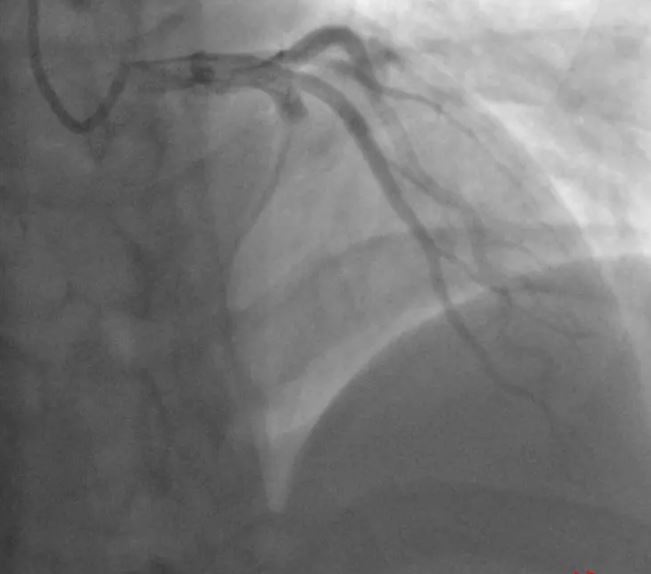

▲小蒲术前的冠脉造影显示,前降支血管严重堵塞

进行紧急冠脉造影,造影结果显示,原本应该粗大明显的冠脉血管前降支的显影只剩下1厘米左右,“前降支被堵死了!”李燕伟告诉记者,前降支又被叫做生命支,承担着左心室的供血功能,这根血管被堵,意味着生命线被堵。